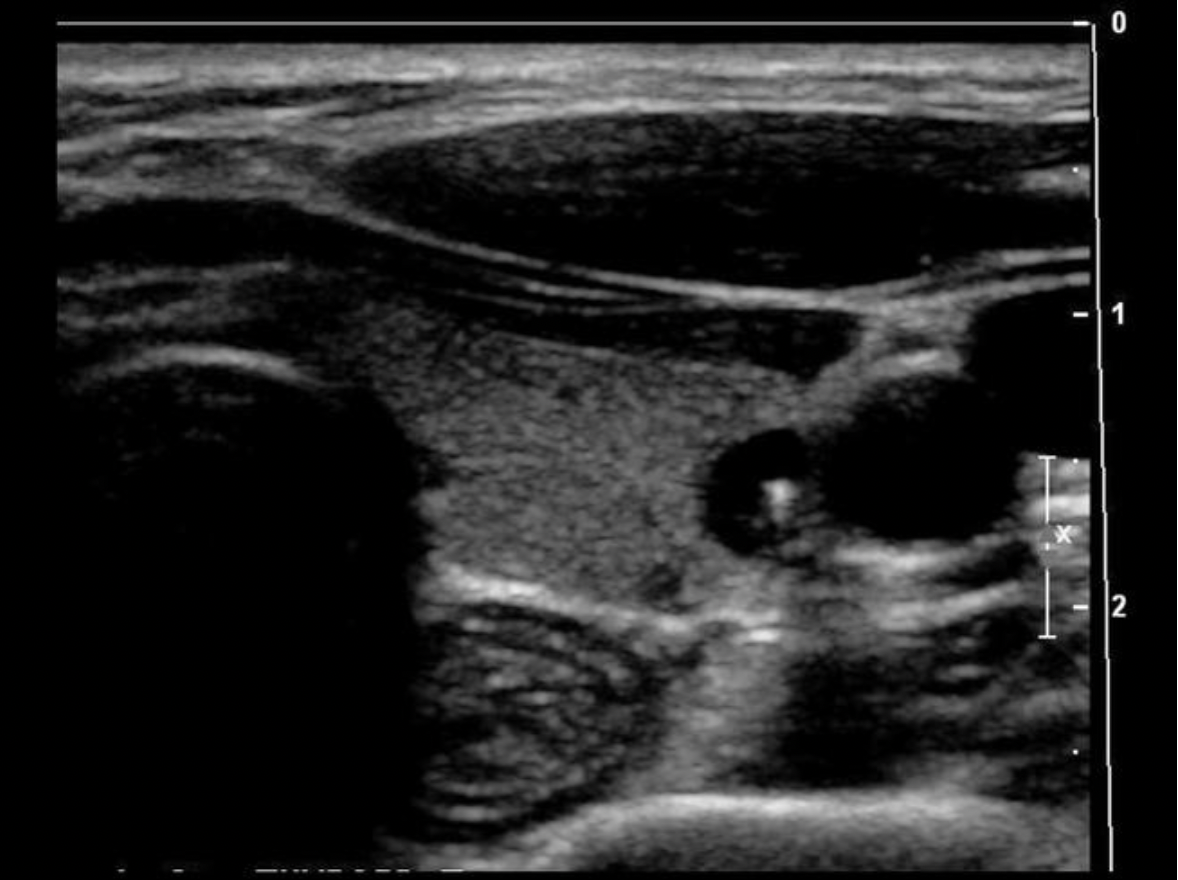

Which of the following is a characteristic of a normal lymph node?

C. thin hypochoic rim with hyperechoic central hilum

Normal lymph nodes are ovoid in shape. They do not demonstrate posterior enhancement. As lymph nodes enlarge with abnormal fluid accumulation, they appear more rounded and hypochoic/anechoic. The "plump" cortex causes decreased visualization of the central hilum. Color Doppler can be used to locate the hilum and main vascular supply. Posterior enhancement is present in structures posterior to abnormal nodes with significant fluid accumulation.

While scanning the thyroid, you identify a 0.6cm ovoid structure outside the thyroid, lateral to the left carotid artery. The structure has a thin hypoechoic rim surrounding a hyperechoic center. These findings are most suggestive of:

D. normal lymph node

Normal lymph nodes are ovoid in shape. They do not demonstrate posterior enhancement. As lymph nodes enlarge with abnormal fluid accumulation, they appear more rounded and hypoechoic/anechoic. The "plump" cortex causes decreased visualization of the central hilum. Color Doppler can be used to locate the hilum and main vascular supply. Posterior enhancement is present in structures posterior to abnormal nodes with significant fluid accumulation.

Find the normal lymph node

A normal lymph node is oval in shape and demonstrates a thin hypoechoic rim of tissue around an echogenic hilum. Abnormal lymph nodes demonstrate a more rounded shape, thickened cortex that can appear anechoic. and there is loss of differentiation of the hilum.